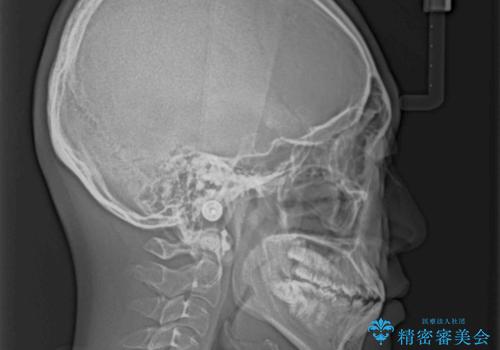

口元の突出感を改善 受け口傾向の咬み合わせの抜歯矯正

- 受け口傾向の咬み合わせと口元の突出感を気にして来院された患者様です。

受け口傾向特有の狭い上顎歯列であったため、歯列の拡大を補助装置で行い、下顎歯列全体を後方に移動させることとしました。

奥歯の咬み合わせを改善させた後、上下左右の小臼歯(下顎は残存乳歯)を計4本抜歯し、ワイヤー装置にて口元の突出感を改善しながら咬み合わせを整えることとしました。